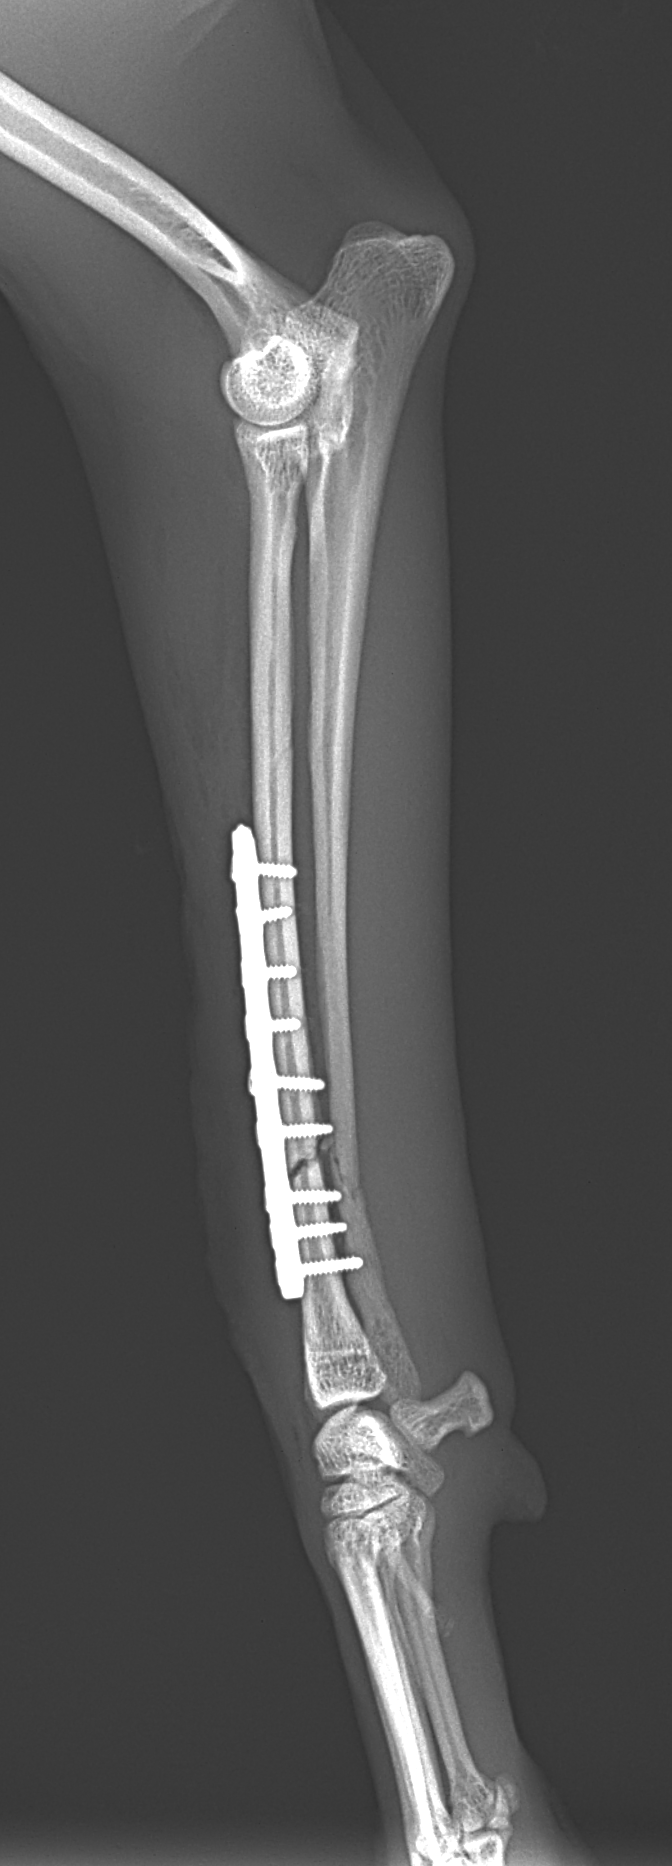

橈骨固定術 #249 Toy Poodleさんがソファーからジャンプして橈骨骨折をしたとのことで主治医の先生から固定術の依頼がありました。1.5 Titanium Locking Plateで固定術を行いました。しばらくは安静が必要です。 症例カテゴリー 放射線治療整形外科軟部組織外科脳神経外科内科腫瘍外科救急・集中治療リハビリテーション科腫瘍内科内視鏡科脳神経科呼吸器外科中医・漢方猫の腎移植循環器科